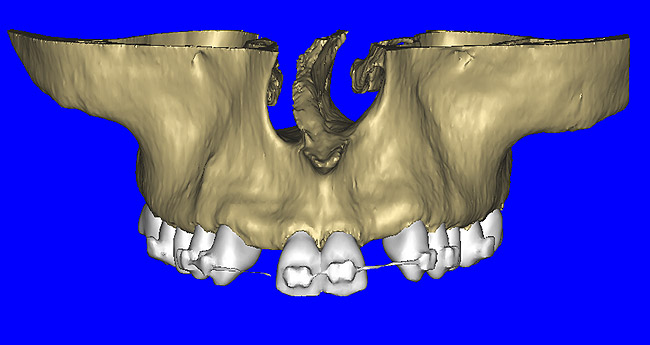

After the basic plan had been established, it was re-evaluated using interactive 3D images. The reconstructed 3D view of the maxilla clearly illustrated the extent of the bilateral facial concavities, and the root eminences of the adjacent and posterior teeth (Figure 7A). The placement of the virtual implants then was evaluated to ensure that the facial cortical plate was not perforated (Figure 7B). The implants were labeled individually as “7” and “10,” with the simulated yellow abutment projection indicating the facial-lingual inclination through the bone to the level above the incisal edge of adjacent teeth. The ability to gain a better understanding of these individual root forms can not be underestimated. The dental literature has suggested certain parameters for placing implants near teeth and implants next to other implants. However, there is little scientific 3D documentation to support these suggested rules.5-10 The use of an interactive treatment-planning software application permits closer scrutiny of previously difficult-to-visualize areas, and can now be used to redefine perceptions of spatial positioning of implants, especially when in close proximity to natural tooth roots, vital anatomy, and adjacent implants.27-29

Figure 7a  The 3D reconstruction showed (A) the facial concavities and root eminences, and allowed (B) for evaluation of virtual implant placement to ensure the facial cortical plate was not perforated.

Figure 7a

Figure 7b  The 3D reconstruction showed (A) the facial concavities and root eminences, and allowed (B) for evaluation of virtual implant placement to ensure the facial cortical plate was not perforated.

Figure 7b